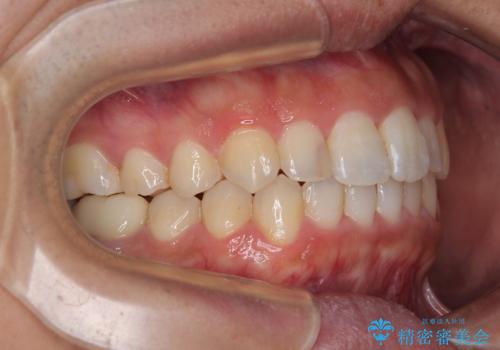

前歯のデコボコと突出感をマウスピース矯正できれいに

矯正治療後に銀歯をセラミックに替えたいとの要望があり、概ね歯列が整ったところで銀歯をセラミックに替え、仕上げにインビザライン1セットを使用して最終的に歯列を整えました。